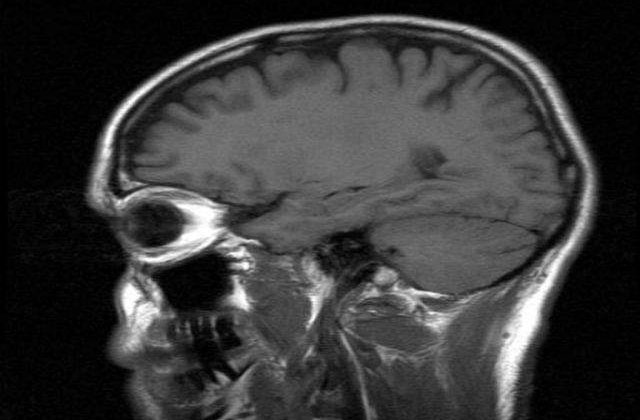

Creierul se regenereaza permanent, nu este "inghetat" si cu cat este stimulat, cu atat obtinem un raspuns bun, a adaugat dr. Dafin Muresanu. Acelasi mecanism, spun specialistii, se dezvolta si atunci cand exista o leziune cerebrala: creierul lupta pentru a se reface. Atunci cand rata de distrugere a creierului este mai mare si rata de refacere sau de stimulare a activitatii creierului este mai dificila.

"Organismul uman are o capacitate incredibila de a se regenera, dar ea trebuie alimentata, stimulata. Pentru ca daca stai degeaba, activitatea creierului se reduce. Fac un apel catre tineri sa citeasca, sa manance mai putina mancare procesata, sa aiba activitate fizica permanenta, sa interactioneze direct si continuu cu oamenii din jur, sa nu fie sclavii tehnologiei. Sa nu ajunga pana acolo incat sa-si trimita SMS-uri dintr-o camera in alta, deoarece acest comportament inseamna dezastru pentru creier", a mai spus medicul.

Potrivit presedintelui SSNN, pentru creier, alimentatia este un factor crucial, alaturi de comportament. "Modul in care ne alimentam este un factor crucial, alaturi de activitatea cognitiva. Trebuie sa avem zilnic activitati din punct de vedere intelectual, sa citim, sa ne activam acea parte din creier care tine de cuvant, nu cea legata de imagine. Componenta emotionala este foarte importanta si trebuie legata de starea cognitiva. De asemenea, cum am spus, alimentatia cat mai aproape de natural, mai putin procesata si fara chimicale, este cea care place creierului", a spus dr. Muresanu.

In acelasi context, specialistul a subliniat faptul ca si creierul are nevoie, periodic, de momente de liniste: "Atat noi, cat si creierul avem nevoie de momente de liniste, de o alternanta intre starile de implicare puternica in viata de zi cu zi si momentele de liniste, de meditatie".